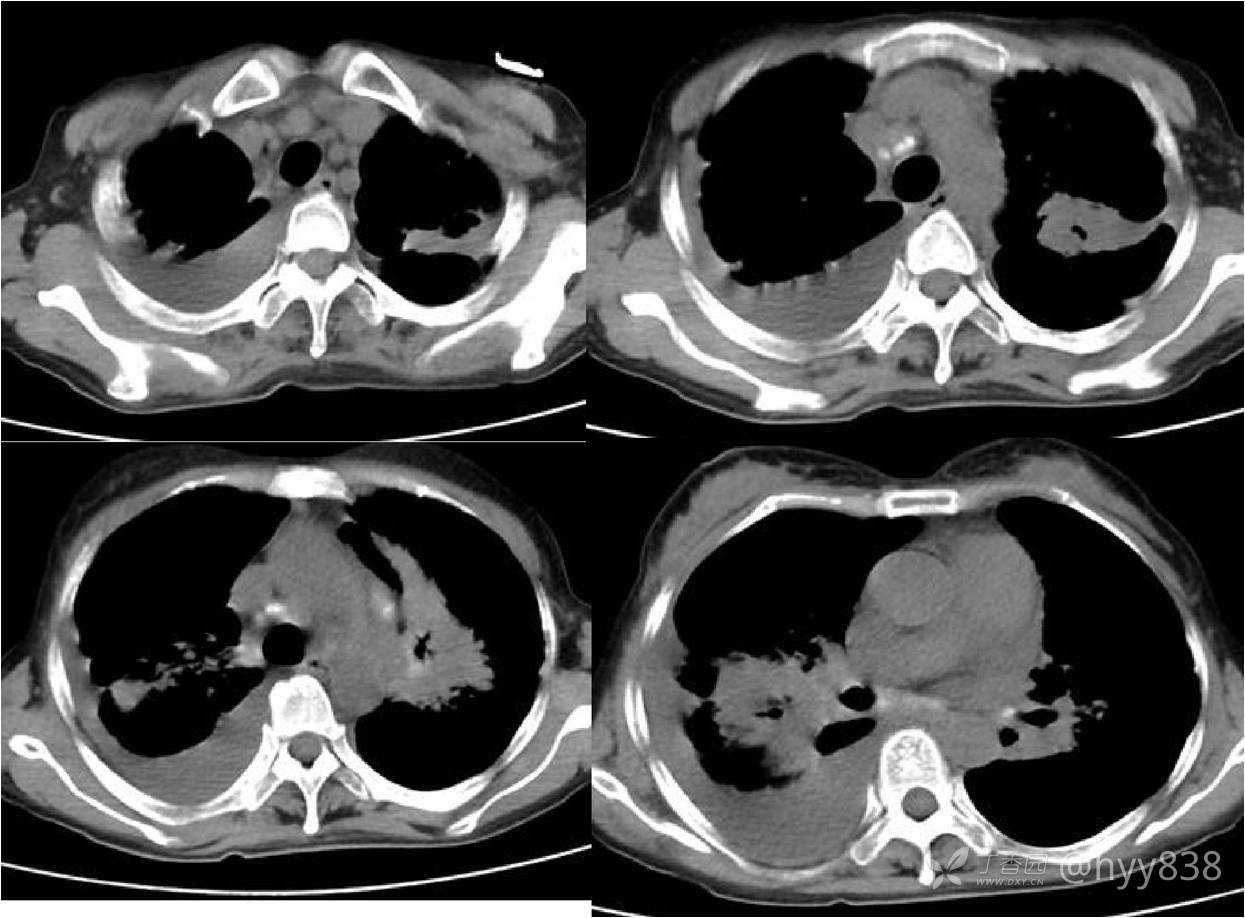

辅助检查:CT

第一次胸部CT